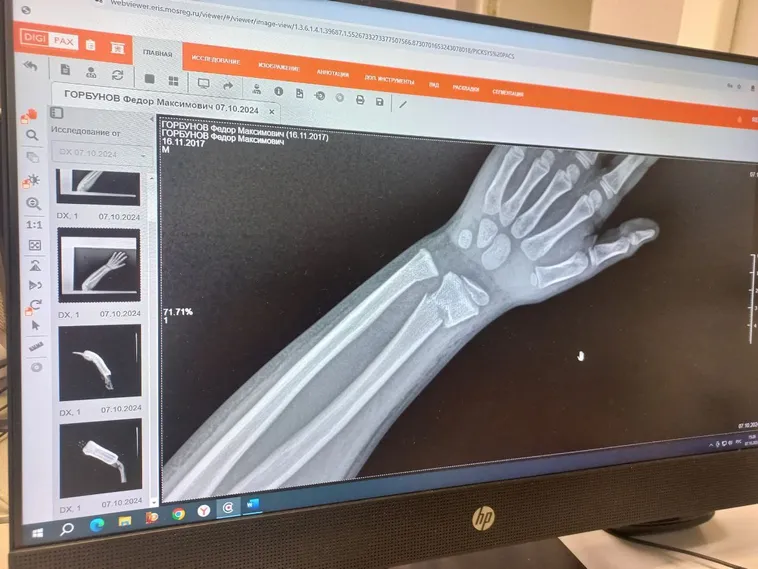

Пример 1: ребёнок, 8 лет, случай максимальной точности консолидации. Перелом двух костей предплечья. Две недели применения методики - акустический контактный резонансный метод Healingbowl® дополнительно к основной терапии. Применялась коллекционная поющая чаша Healingbowl® Luxury Mustang®, частота около 130 Гц. Это было пробное лечение под руководством Виктора Петровича, всё согласовано с родителями.

Применение чаши по методике доктора Сурикова позволило ускорить регенерацию в какой-то степени, регенерация шла на очень высоком уровне. Получен дополнительный седативный эффект, ребёнок быстро засыпал, чаши не боялся. Вибрация обезболила, убрала отек, улучшила дренажную функцию, способствовала сокращению сроков регенерации тканей.